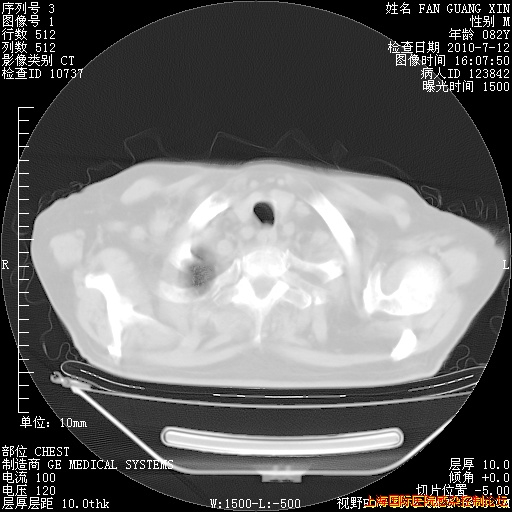

今天复查CT

今天CT

整整相隔30天的肺部CT好像有所好转啊。甲强龙减量第3天,需要观察体温。